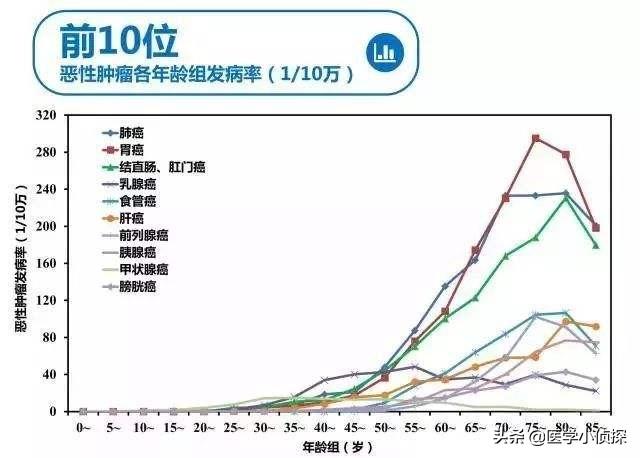

いわゆる胃がんは、間違いなく私たちの体内に発生する。胃部悪性腫瘍のしかし、胃の悪性腫瘍は胃癌とは異なることに注意すること。つまり、胃に発生する悪性腫瘍は、おなじみの胃がんに加えて胃リンパ腫、胃間葉系腫瘍など他の悪性腫瘍もある。しかし、胃がんは胃の悪性腫瘍の中で最大の数を占めている。95%以上さらにわが国は有病率が高い.わが国ではここ数年、胃がんの罹患率は低下しているが、胃がんの罹患率は依然として高い。胃がんによる死亡者数は特に激減していない。男女ともに胃癌の発生率は悪性腫瘍の中で2番目と5番目に高く、死亡率は3番目と2番目に高い。55~70歳が有病率の高い年齢層である。。